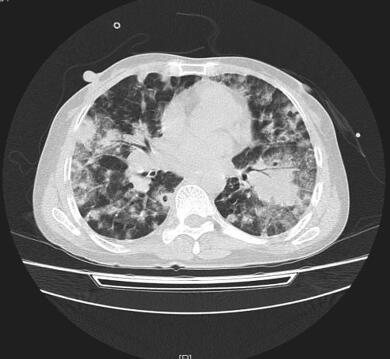

入院后检查:生命体征尚平稳,急性病容,呼吸急促,有发热,体温38.6℃,双肺散在湿性啰音。心律齐,心率快,114次/分,各瓣膜听诊区未闻及杂音,腹部无明显阳性体征,双下肢无水肿。脑膜刺激征阴性,病理征未引出。血常规:WBC 18.3×109/L,N% 94.1%,HGB 108g/L,PLT 130×109/L。红细胞沉降率:96mm/h。PCT 18.7ng/ml,BNP 15 200pg/ml,肝肾功能未见明显异常。低钠血症,低钾血症,结核菌素试验(+)。3次痰抗酸染色未见抗酸杆菌。3次痰培养未发现致病菌。血气分析(吸氧2L/M)提示:pH 7.492,PaO2 59.3mmHg,PaCO2 16.3mmHg。抗核抗体(ANA)、ANA谱、dsDNA抗体及抗中性粒细胞抗体均正常。钩端螺旋体抗体、恙虫病抗体、流行性出血热抗体均阴性。真菌D-葡聚糖+曲霉菌半乳甘露聚糖抗原:均正常。HAV+HIV+HCV+TPPA抗体:均正常。呼吸道感染病原体IgM抗体:呼吸道合胞病毒-IgM抗体阳性(+),余均阴性。(2014年6月29日)肺部CT平扫(图1):):①双肺弥漫性病变伴空洞形成,肺炎并脓肿?肉芽肿性病变?②左下肺脓肿形成。

图1 2014年6月29日胸部HRCT

双肺弥漫性病变伴空洞形成,左下肺脓肿形成